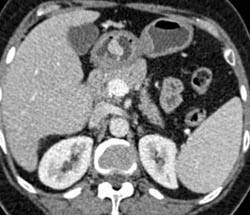

Linitis Plastica